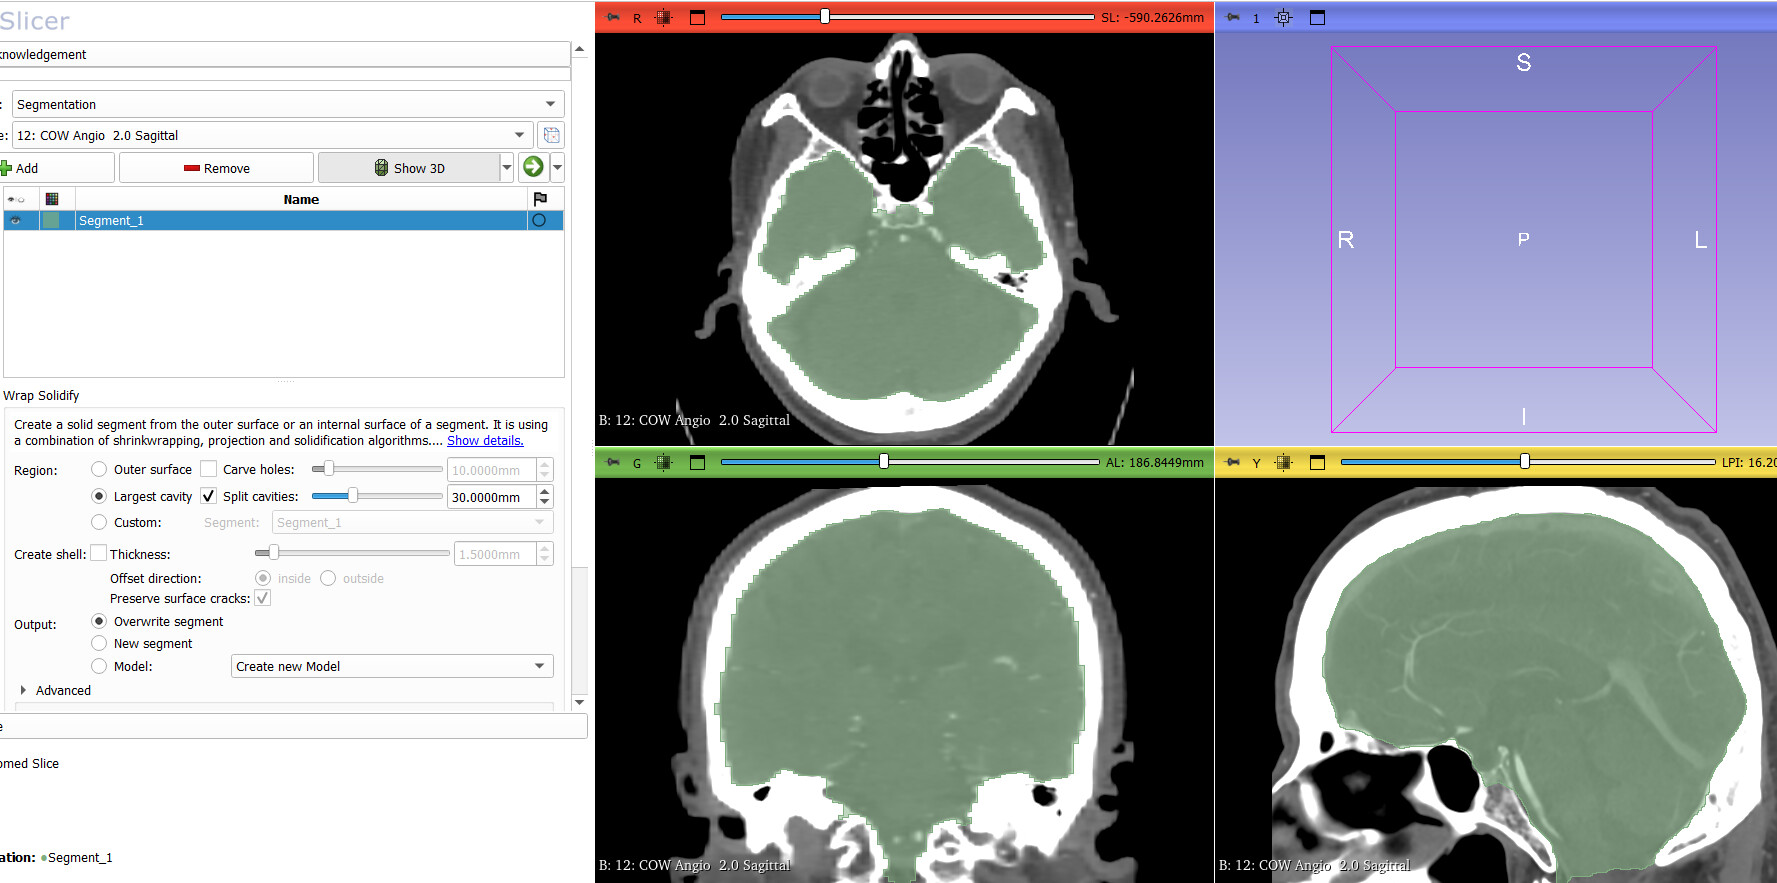

I would like to automatically extract the brain from CT angiograms using a Python script. I have tested the WrapSolidify extension in 3D Slicer, and it works well (see screenshot). My questions are :